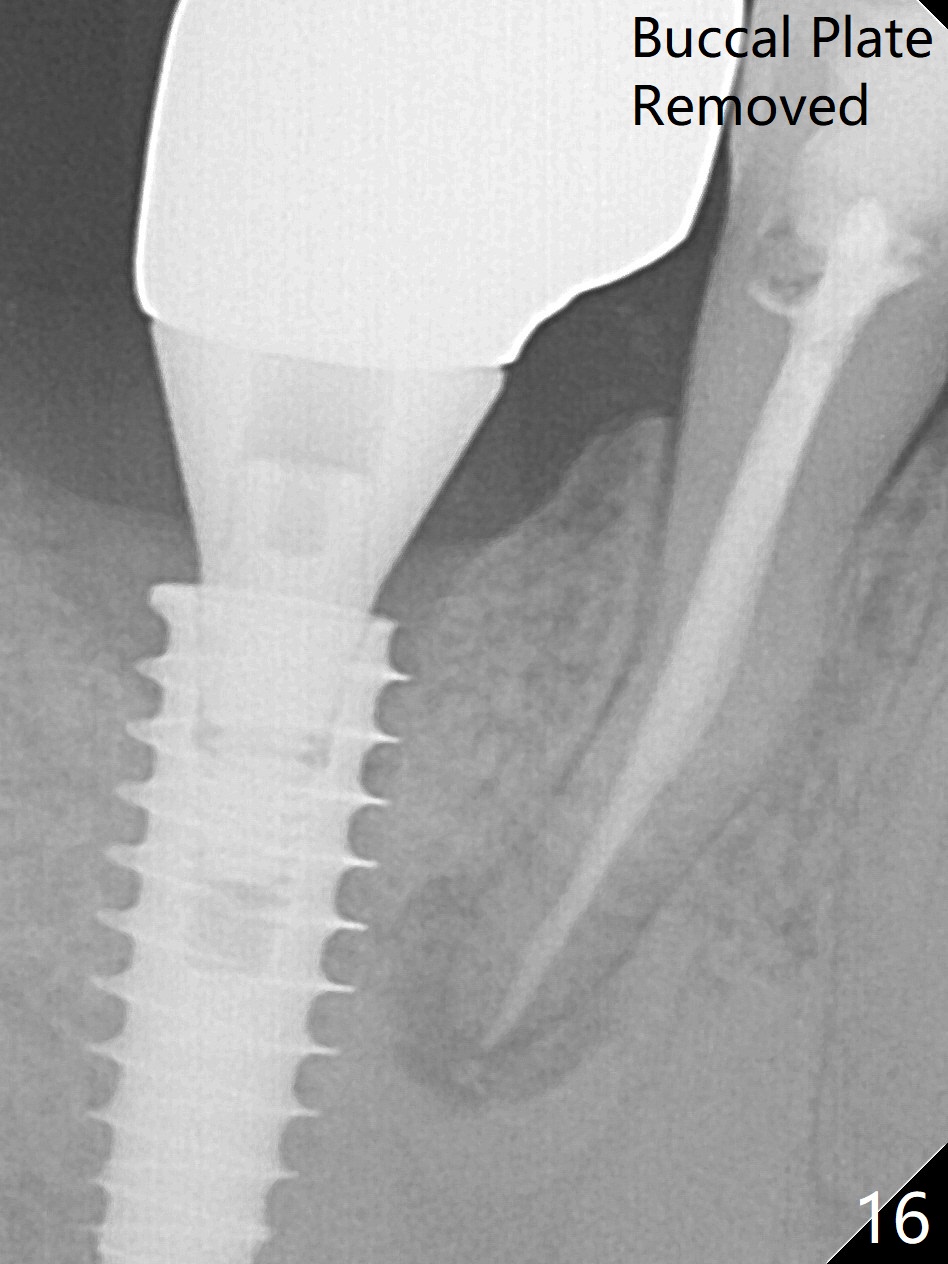

Bone graft seems to sink down and becomes denser 3 months postop (Fig.6 arrow). The bone continues being denser 5 months postop (Fig.7). There is periapical radiolucency of the tooth #29 (^). RCT is done (Fig.8). The pain persists 2 weeks postop (Fig.9,10). There is no missing canal (Fig.9). The apex is close to the implant (Fig.9 *). Apicoectomy will be performed if needed. It appears that the implant is also placed buccal (Fig.10 <) and/or the implant too large for the site. Therefore there should be a 2-3 mm buccal gap before and after implant placement. Separation and reflection of the buccal flap allows better visibility. The pain persists 1 month post RCT and 6 months post implant placement. RCT retreatment is initiated (Fig.11,12) with placement of Calcium Hydroxide paste after redebridement with 30/.04 rotary file at 23.5 mm (.5 mm longer than the earlier RCT, Fig.13). RCT retreatment finishes with apparent transportation and extrusion in 4 weeks (Fig.14,15), followed by apicoetomy (Fig.16,17) (20 days later)). Discomfort remains 2.5 months postop (Fig.18). Keep watching.